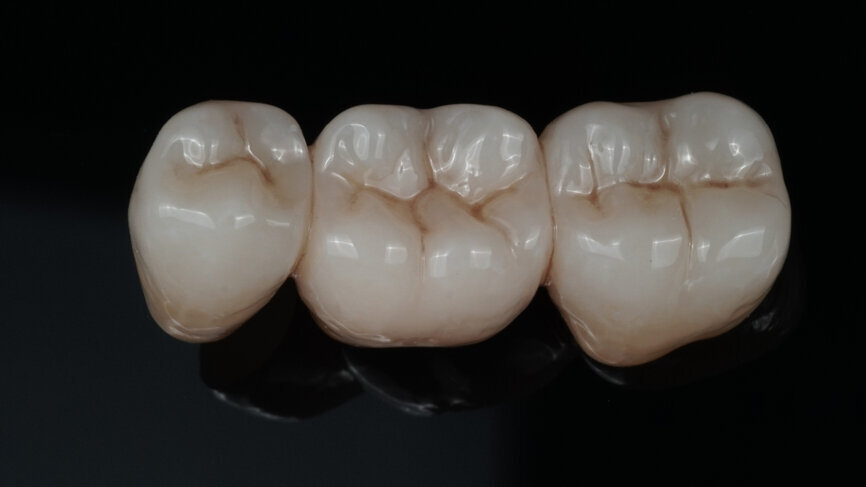

Fig. 7: Surface texturing in the pre-sintered state (prior to the final sintering procedure).

Fig. 8: Bridge after a 7-hour sintering cycle.

Fig. 9: Appearance of the bridge after individualisation with CERABIEN ZR FC Paste Stain.

Fig. 10: Appearance of the bridge after two glaze firings.